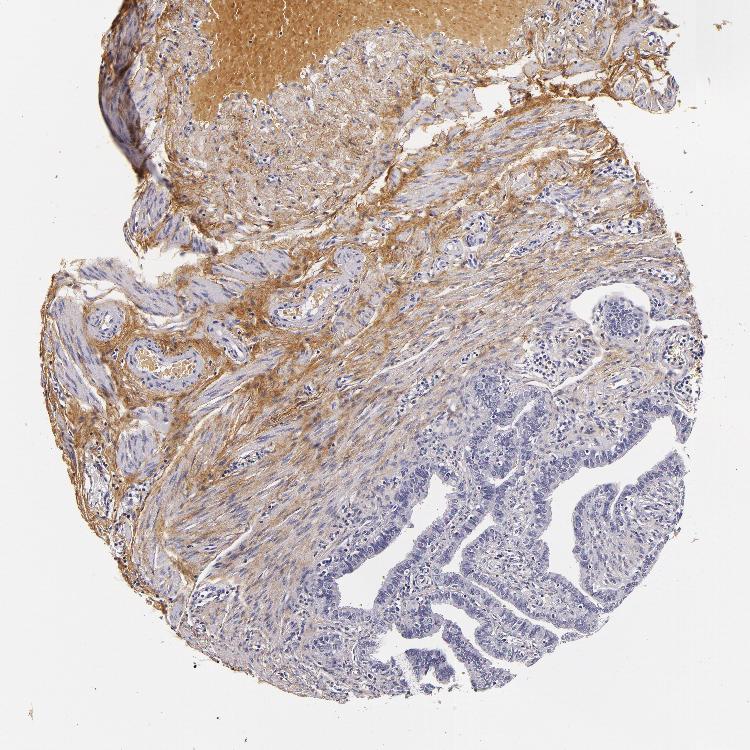

FALLOPIAN TUBE - Antibody stainingi

Antibody staining in the annotated cell types in the current human tissue is reported as not detected, low, medium, or high, based on conventional immunohistochemistry profiling in selected tissues. This score is based on the combination of the staining intensity and fraction of stained cells.

Each image is clickable and will lead to virtual microscopy that enables deeper exploration of all samples and also displays staining intensity scores, fraction scores and subcellular localization as well as patient and tissue information for each sample.

Antibody HPA017759Antibody HPA021057Antibody CAB002670Antibody CAB058696Antibody CAB068188Antibody CAB080202

Glandular cells LowNot detectedNot detectedNot detectedNot detectedNot detected